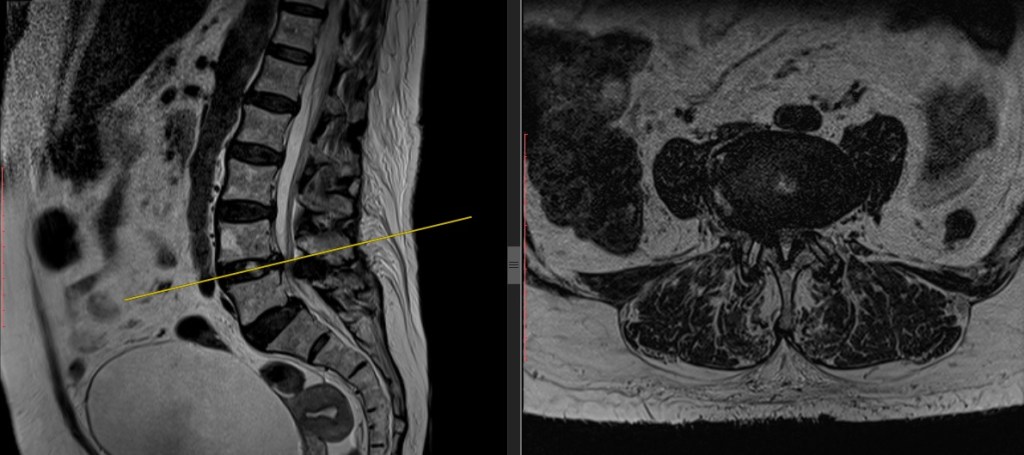

Se define por el estrechamiento del canal raquídeo, lo que condiciona la compresión de las raíces nerviosas que se dirigen a las extremidades inferiores. Aparece sobre todo a nivel L4-L5 seguido de L5-S1 y L3-L4. Tiene lugar fundamentalmente en personas mayores de 60 años y se debe a la progresiva degeneración de las articulaciones y ligamentos que unen las vértebras. Este proceso de desgaste genera un aumento o hipertrofia que deforma dichas estrucuras de manera que invaden el espacio destinado a las raíces nerviosas provocando la compresión e irritación de las mismas. Esto se traduce en la aparición de un dolor lumbar irradiado a ambas regiones glúteas y en ocasiones a ambas extremidades inferiores.